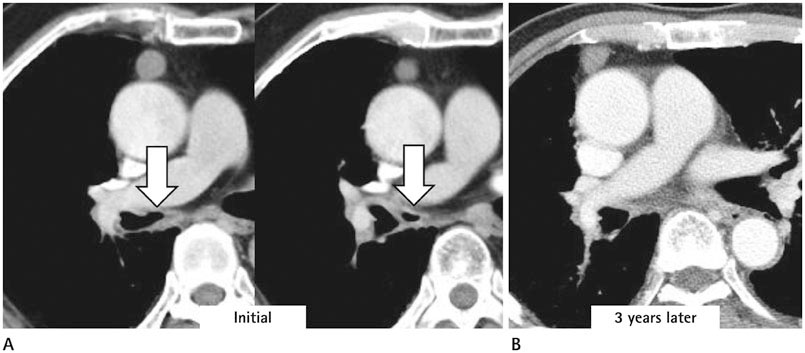

We identified two main types of ACB: blind-end (51.7%) and lobule (48.3%). The blind-end ACB was further classified into three subtypes: blunt (70%), pointy (23.3%) and saccular (6.7%). The lobule ACB was also further classified into three subtypes: complete (46.4%), incomplete (28.6%) and rudimentary (25%). Division location to the upper half bronchus intermedius (79.3%) and medial direction (60.3%) were the most common in all patients. The difference in division direction was statistically significant between the blind-end and lobule types (p = 0.019). Peribronchial soft tissue was found in five cases. One calcification case was identified in the lobule type. During follow-up, ACB had disappeared in two cases of the blind-end type and in one case of the rudimentary subtype.

The proposed classification of ACB based on imaging, and the follow-up CT, helped us to understand the various imaging features of ACB.